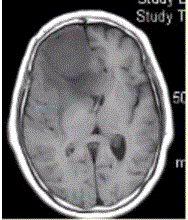

问题 女,64岁,发作性意识丧失,左侧肢体无力,MR显示右侧额叶等T1信号影(下图),病变明显强化,最可能的诊断是

选项 A.室管膜瘤 B.星形细胞瘤 C.脊索瘤 D.脑膜瘤 E.转移瘤

答案 D